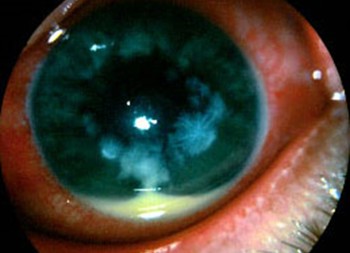

The majority of fungal CLMK infections are caused by Fusarium, Aspergillus and Candida species2, with an insidious course similar to Acanthamoeba keratitis. Fungal species exhibit a diverse range of morphologies and a constellation of presentations can be seen, including the classic description of a poorly defined fluffy infiltrate edged with satellite lesions (Fig 2). Extensive and deeply buried hyphae pose special challenges as they are too large to be ingested by host immune cells and require deeply penetrating antifungal formulations. The main risk factor is ocular trauma involving organic matter6 and thus a history of trauma should be documented. Thankfully, New Zealand has relatively low rates of fungal keratitis, with 2-5% positive on corneal scrapes3, 7.

Fig 2. Fusarium keratitis with ill-defined infiltrate, satellite lesions and hypopyon